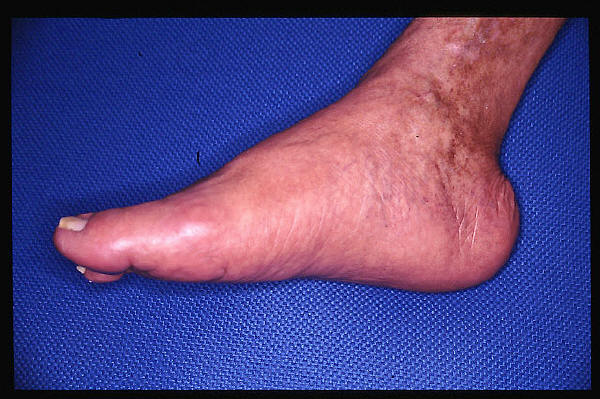

Insuficiencia venosa crónica